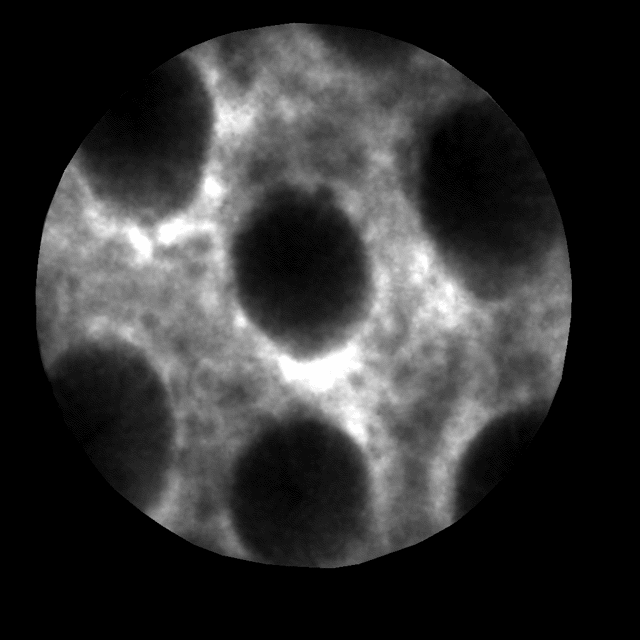

共聚焦激光显微内镜临床图像

而共聚焦激光显微内镜的出现,可以为传统病理检测提供靶向活检,减少活检带来的组织损伤。基于激光扫描共聚焦显微镜成像原理,它在活体内实现了细胞级别的高分辨率成像效果,内镜医师可以实时观察到在体细胞画面,实现无创的“光学活检”。

共聚焦激光显微内镜观察胃粘膜

例如,在白光内镜下,早期胃癌不易识别,或仅表现为黏膜局部色泽的改变,稍显僵硬、或呈颗粒状、触之易出血等,往往难以与炎症性病变鉴别。但有了共聚焦激光显微内镜后,“光学活检”可以融入进内镜检查中,大大提升内镜检查的精度,成为快速可靠的“扫癌利器”。